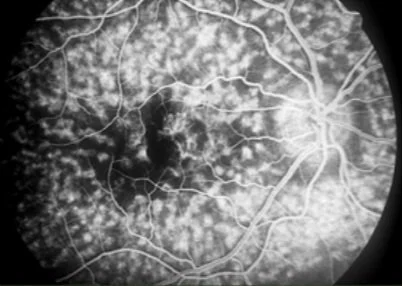

• Cystoid appearance (inside the macula, aflower petal appearance because of the organization of the outer plexiform layer; outside of the macula, a honey- comb appearance): diabetic retinopathy, telangiectasis, choroidal or retinal inflammation, subretinal neovascularization, subretinal inflammation, choroidal tumours.

• Non-cystoid pattern (usually due to small retinal vessel leakage): hypertension, diabetes, or vasculitis.